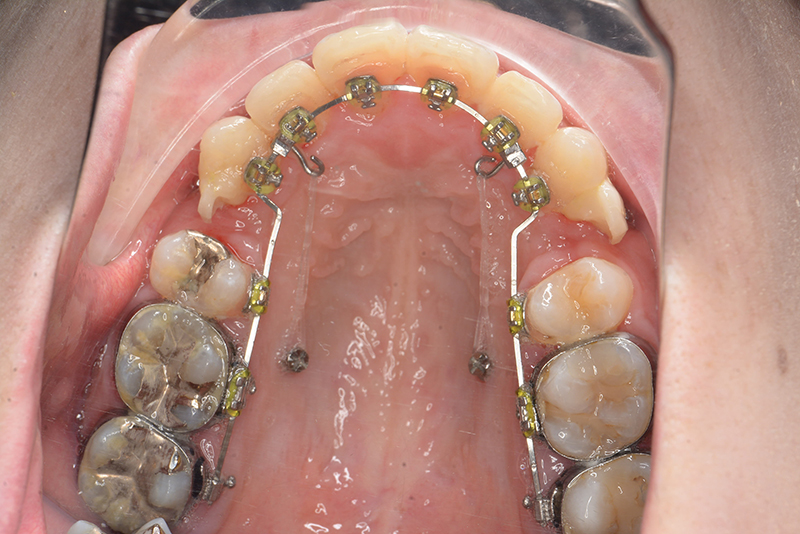

動的治療中のIOP(治療開始後6ヶ月)

動的治療中のIOP

(治療開始後6ヶ月)

IOP